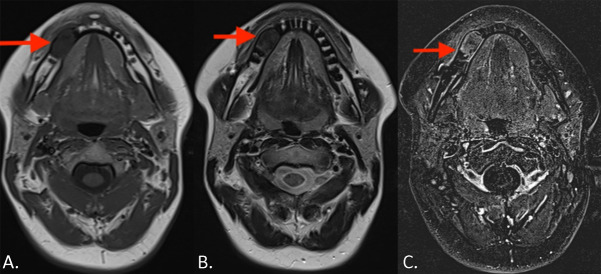

教学点:骨水泥骨化纤维瘤是颌骨的一种良性肿瘤,具有混合透光-不透光外观,引起牙根吸收和骨扩张。

Teaching point: Cemento‑ossifying fibroma is a benign tumor of the jaws with a mixed radiolucent-radiopaque appearance and causes root resorption and bone expansion.